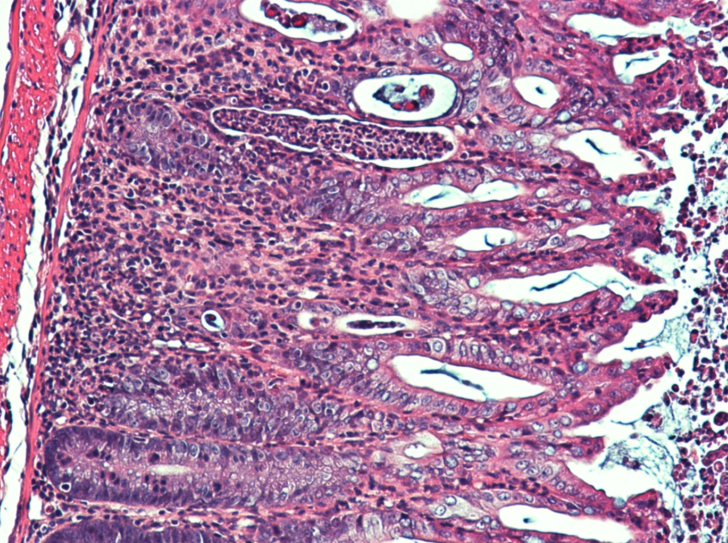

Maladies inflammatoires de l’intestin : les cellules immunitaires, fer de lance de la guérison

Les inflammations de l’intestin touchent de nombreux patients, avec des perspectives thérapeutiques souvent réduites. Le rôle du fer dans ces…